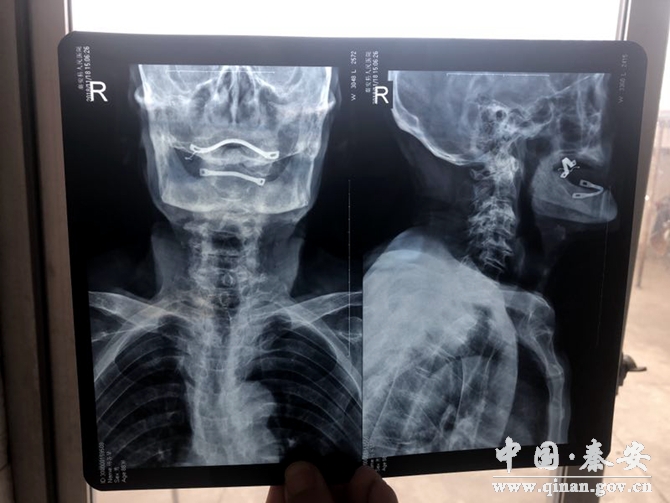

其中一位72歲女性住院患者,主因“頸部不適伴頭昏頭暈3年余,加重1天”收住。無高血壓,冠心病病史。平時不能坐立看電視,不能俯臥。服藥兩年,沒有明顯效果,來診后應(yīng)用針刀微創(chuàng)治療,松解減壓,病人頭昏頭暈明顯減輕,偏頭痛基本消失。

目前頸椎病的保守治療較多,但見效較慢,療效甚微,針刀閉合松解術(shù)的出現(xiàn),給頸椎病患者帶來了福音,針刀直接解除頸部病變組織的瘢痕,粘連、攣縮、堵塞,使頸段脊柱生物力學(xué)平衡得到有效恢復(fù),解除對神經(jīng)根及椎動脈的刺激,則疼痛、眩暈等癥狀緩解或消除,治療過程操作簡單,見效快,切口小,痛苦少,治療效果明顯,避免西藥對人體的危害。